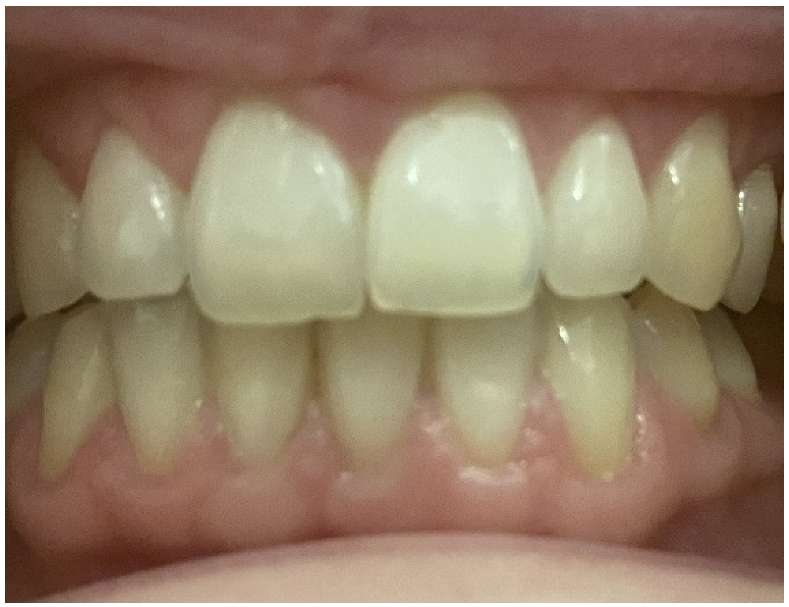

2. Case Report

2.3. Oral Examination